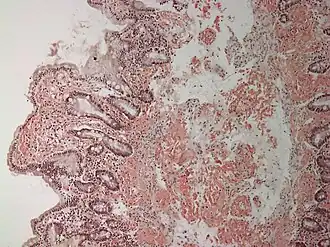

![]() Микроскопическая картина патологоанатомического препарата с развившимся амилоидозом | |

Микроскопическая характеристика

Амилоид в микропрепаратах выглядит как аморфная эозинофильная масса, которую можно дифференцировать от гиалина специальной окраской и характером накопления в ткани. При использовании красителя конго красный амилоид избирательно выкрашивается в красный цвет, однако для исключения ложноположительных результатов используют исследование в поляризованном свете.